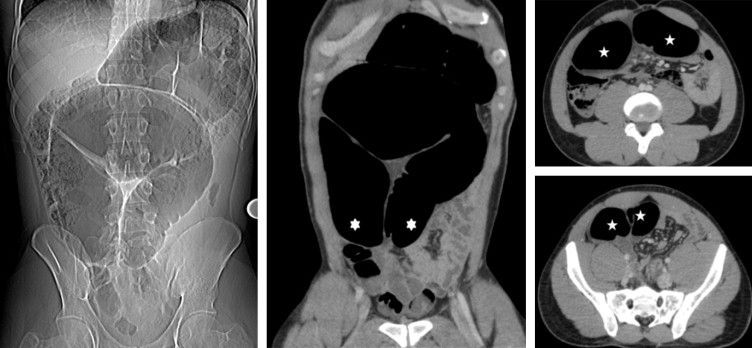

Closed loop obstruction is a phenomenon characterized by obstruction of the bowel at two points. The obstruction usually occurs secondary to adhesions, herniation, or volvulus. Reference: https://radiologyassistant.nl/abdomen/bowel/closed-loop-in-small-bowel-obstruction#:~:text=Closed%20loop%20obstruction%20is%20a,is%20known%20as%20a%20volvulus. Image via: https://www.sciencedirect.com/science/article/pii/S2211568413003318